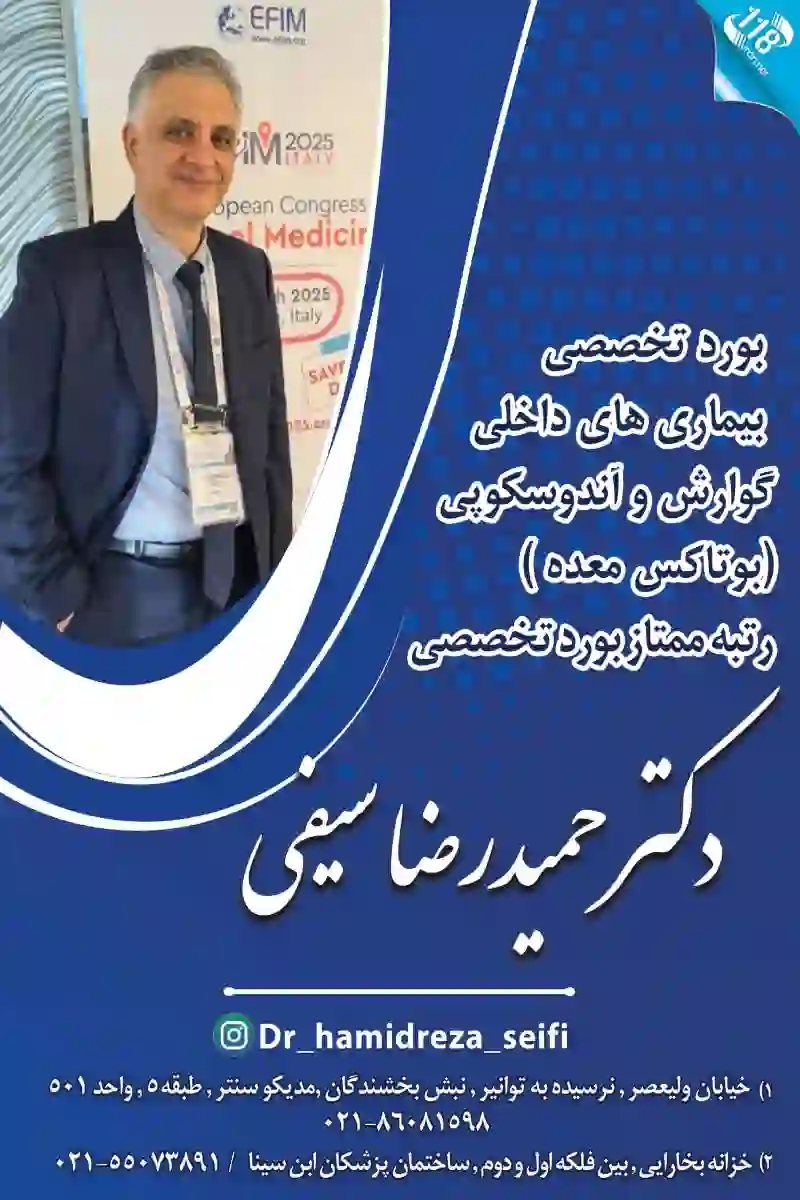

مطب دکتر حمیدرضا سیفی

کد نظام پزشکی: 39824 بنده دکتر [نام] هستم و تخصص من بیماریهای داخلی، گوارش و اندوسکوپی است. من عضو انجمن گوارش و کبد ایران هستم و دارای بورد تخصصی داخلی از دانشگاه شهید بهشتی تهران میباشم.

استان: تهران ، شهر: تهران ، منطقه 16 ، محله: خزانه ، خیابان: خزانه بخارایی ، کوچه: بین فلکه اول و دوم،ساختمان پزشکان ابن سینا ، طبقه: 0